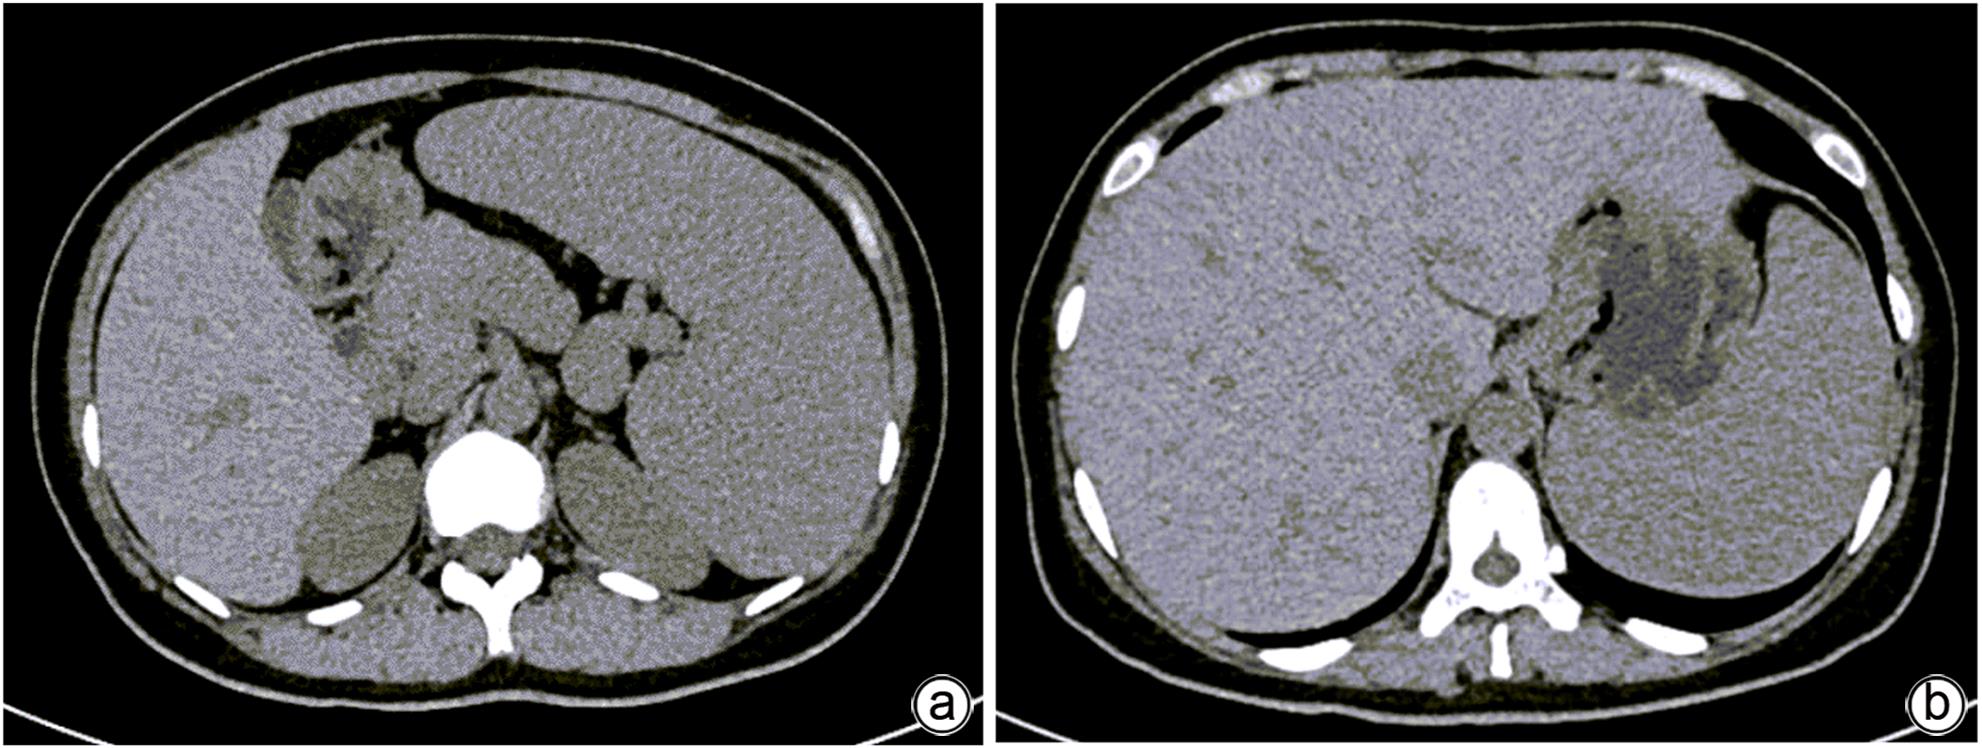

Niemann-Pick disease type B and heterogeneous manifestations of its liver involvement: A case report

Qiao YANG, Yi SHEN, Yue SHI, Jin WANG, Fangfang LYU

2024, 40(2): 356-360. DOI: 10.12449/JCH240221

Abstract(1057) HTML (374) PDF (1123KB)(121)

Abstract:

This article reports a case with the chief complaint of “hepatosplenomegaly to be investigated” and a confirmed diagnosis of Niemann-Pick disease type B after various tests, and a literature review was conducted to summarize the heterogeneous manifestations of liver involvement in type B Niemann-Pick disease, in order to improve the clinical management of difficult and rare liver diseases.